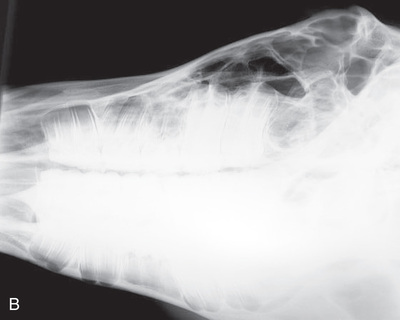

| Cervical spine | Lateral (Fig. 24.58) | Side of the cervical region. | Opposite side of neck. | Centered on region of choice: | Because of the size of the patient, the cervical spine must be exposed in three views. The patient can be standing or recumbent. |

| Thoracic spine | Lateral (Fig. 24.59) | Side of the patient on area of interest. | Opposite side. | Area of interest perpendicular to the image receptor. | Often completed for the dorsal spinous processes (withers). |